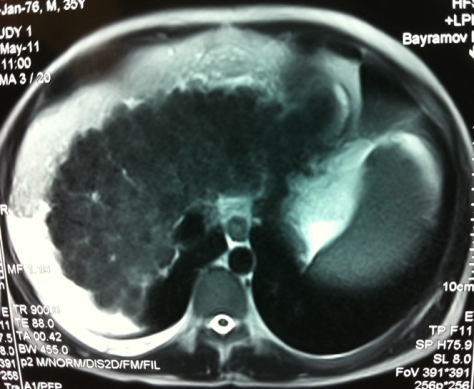

NEYROENDOKRİN TÖRƏMƏLƏRİN QARACİYƏRƏ METASTAZLARI

N.Y.Bayramov, R.A.Məmmədov

Tərifi

Orqan və toxumalarındakı yerli endokrin hüceyrələrindən (karsinoidlər) və mədəaltı vəzidəki (MAV) adacıq hüceyrələrindən inkişaf edən şişlərin qaraciyər metastazlarıdır.

Ümumi xarakteristika

• Neyroendokrin törəmələr (NET), orqan və toxumalarındakı yerli endokrin hüceyrələrindən və mədəaltı vəzidəki (MAV)adacıq hüceyrələrindən inkişaf edən şişlərdir.

• Bunlara APUD-omalar da deyilir

• Klassik olaraq NET-lər iki qrupa bölünür: karsinoid və qeyri-karsinoid şişlər.

• Tərkibində neyronal enolaza enziminin olması sinir mənşəli olduqlarını göstərir.

• Hormonal aktiv və ya qeyri-aktiv formaları ola bilir.

• NET-lərin bəd və xoşxassəli formaları sitoloji və histoloji cəhətdən fərqlənmir, bədxassəliyin yeganə əlaməti metastazların olmasıdır.

• NET-lərin hamısında xromoqrafin A və neyron spesifik enolaza tapılır ki, bu da diaqnozu dəqiqləşdirə bilir.

Gedişi

• NET metastazları yavaş böyüyən, kimyaterapiyaya az həssas törəmələrdirlər, adətən hipervaskulyar olurlar və sürətli qan axınına sahibdirlər.

• NET-in təbii gedişinə təsir edən ən önəmli amillər qaraciyərə metastaz, metastazların sayı və müalicədir: 5 illik yaşam metastaz olmayan hallarda 90-100%, metastaz olduqda 30-40%,  rezeksiyadan sonra 70%-ə çata bilir.

Diaqnostikası

Dəqiqləşdirmə

• Dəqiqləşdirmək üçün klinik əlamətlərlə yanaşı endokrin müayinə, tomoqrafiya və ssintoqrafiya aparılır.

• NET-in qaraciyər metastazlarının xarakterik xüsusiyyəti hipervaskulyar olmasıdır ki, bu da Doppler müayinəsində intensiv axın şəklində, kontrastlı müayinələrdə isə arterial fazada kontrastlaşma və venoz fazada yuyulma əlaməti ilə təyin edilir.

• Hormonal aktiv şişlərdə endokrin əlamətlərlə yanaşı qanda hormonların səviyyəsi artır.

• Funksional karsinoidlərdə sidikdə 5-hidroxiindol turşusunun təyini, adacıq şişlərində isə hormonların təyini diaqnozda faydalıdır.

• Adacıq şişlərinin yayılmasını və diaqnozunu dəqiqləşdirmək üçün PET-KT və somatostatins sintoqrafiyası faydalıdır.

• Histokimyəvi müayinədə xromoqrafin A və neyron – spesifik enolazanın tapılması diaqnozu dəqiqləşdirir.

Diaqnostik əlamətləri:

• Kütlə effekti və ya endokrin əlamətlər

• 5-hidroksiindol turşusu və ya hormonların artması

• Hipervaskulyar törəmələr

• PET-KT və ya somatostatin ssintoqrafiyası müsbət

• Biopsiyada xromoqrafin A, neyronal enolaza enzimi müsbət